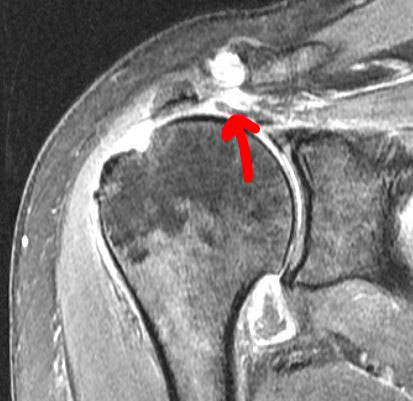

Supraspinatus Tendon Tear

Tear is on the left and the healed repair is on the right